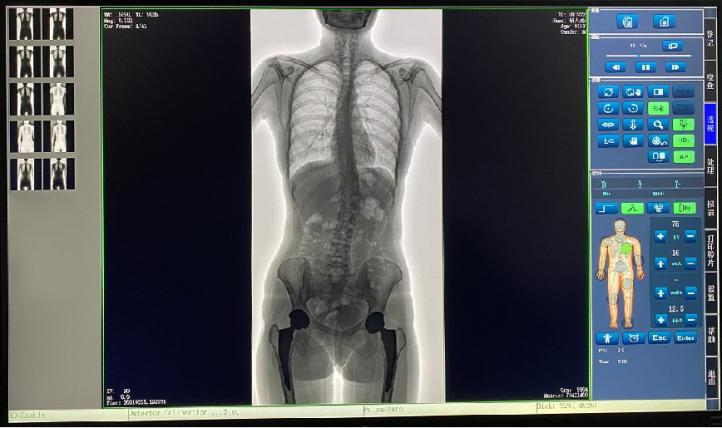

普爱医疗新推出一款动态平板DR-PLX8600,这款产品可摄影、可透视、可造影,临床适用范围广泛,可满足不同临床拍摄需求。一体式的机架,摆位简单快捷,不仅融合了市面上17英寸动态DR的所有功能,还有独具特色的超大动态视野范围,给临床应用带来医疗诊断价值,降低医院设备投入成本,获得更大收益。

1.专为大视野临床应用打造的平板动态DR,图像不拼接,有效简化影像科室检查流程,提高诊断精度,降低患者吸收的辐射剂量。

2.解决了拼接图像存在密度不均匀,拼接处图像配准和放大效应等问题,辐射剂量小。